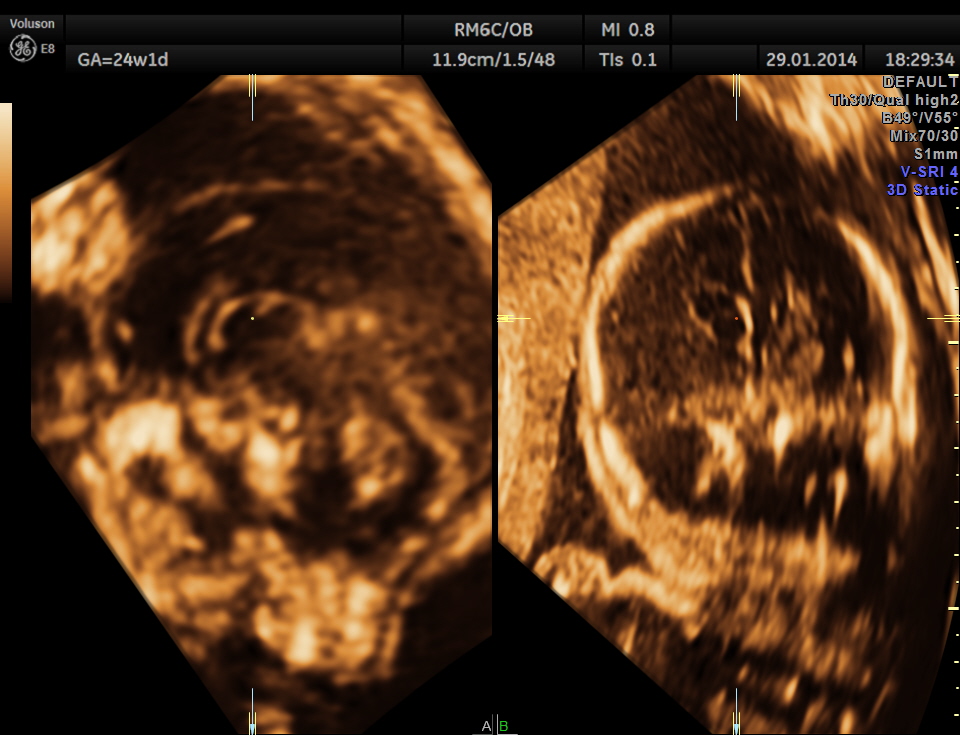

This was a 32-year-old lady – primi gravida . She was referred for an anomaly scan around 24 weeks gestation.Her earlier scan done in the first trimester elsewhere was reported as normal.

The following images were obtained. Unilateral choroid plexus cyst was seen .

Images of the other organs are given below.